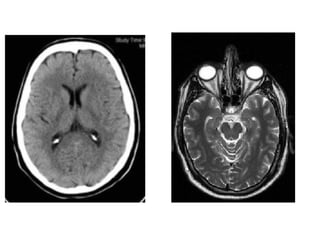

Corno Frontal III Ventrículo  Forames de Monro Corno  Temporal Corno  Occipital Aqueduto de Sylvius IV Ventriculo Canal ependimal central

Corno Frontal IIIVentrículo Forames de Monro Corno Temporal Corno Occipital Aqueduto de Sylvius IV Ventriculo Canal ependimal central